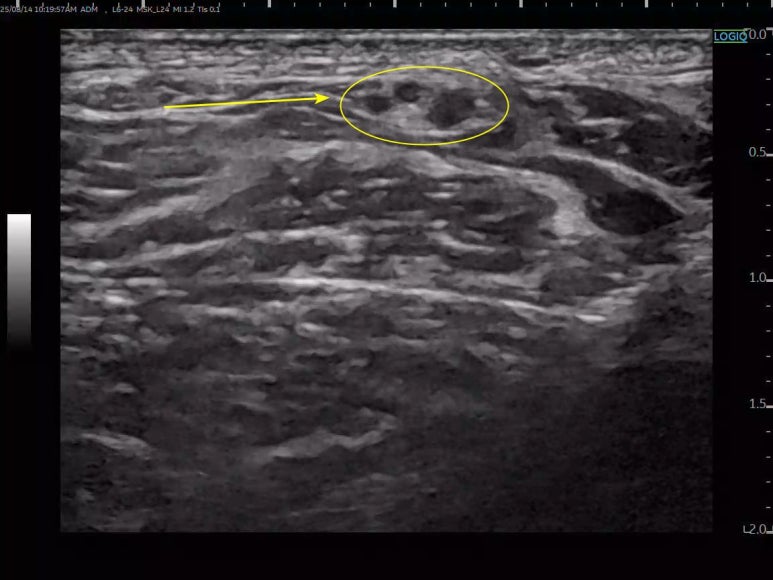

두번째, '속으로 곪은 신경'입니다. 이건 좀 더 까다로운 경우인데요. 신경의 전체적인 크기는 정상이지만, 신경을 구성하는 수많은 가닥 중에 특정 가닥 몇 개만 부어있는 상태입니다. 마치 굵은 전선 속의 구리선 몇 가닥만 녹슬어 버린 것과 같죠. > 비골신경마비 증상 > > 신경병증성 통증 비골신경이 눌리거나 손상되면 해당 신경이 지배하는 부위에 운동 기능 저하 / 감각 이상이 나타나는데요. *특히 운동기능에 문제가 생긴 경우, 움직임에 따른 찌릿한 통증

양릉천 혈자리를 관찰해보면 비골신경이 피부에 가깝게 위치하고 있어 부딪힘에 의해 쉽게 손상될 수 있고요. 그 아래로는 뼈와 점점 더 가까워지기 때문에 단단한 뼈나 주변 조직 사이에 쉽게 포착됩니다. *그렇기 때문에

*이 위치에서 비골신경이 가장 많이 눌리고 손상되는 것이죠. > 비골신경마비 치료 > > 초음파 약침 자, 이제 문제의 원인을 찾았으니 어떻게 치료할까요? 혈자리에 약침액을 주입하여 경혈과 한약의 시너지 효과를 내는 치료는 단순히 유착을 풀어주는 물리적인 효과를 넘어, 신경 자체를 회복시키는 놀라운 힘을 가지고 있습니다. 양릉천 혈자리 주변의 증상과 촉진으로 해당 문제를 확인한 뒤에 초음파 프로브를 대고요. 유착된 부위 바늘을 안전하게 위치시킨 뒤 약침을 천천히 주입하여 신경을 옥죄고 있던 주변 조직을 살살 떼어내는 거죠. 특히, PDRN 연아약침은 연어에서 추출한 DNA 성분으로 재생과 염증완화 효과가 뛰어난데요. 과민해진 신경의 통증 스위치를 진정시켜통증 자체를 줄여주고, 유착 때문에 굶주리고 지쳐있던 신경에 직접 영양분을 공급해 신경이 스스로 회복할 힘을 길러줍니다. > 족하수 치료 원인모를 만성 통증과 저림은 신경이 주변 조직에 눌리고, 유착되어 생기는 경우가 많습니다. 만약 당신의 발목에 힘이 없고 정강이, 발등이 이유없이 저리다면, 양릉천(陽陵泉) 혈자리 부근에서 비골신경이 눌려있을 가능성이 있습니다. 신경이 '퉁퉁 부었는지', 아니면 '속으로 곪았는지' 명확하게 진단하고, 안전한 약침 시술을 통해 신경의 숨통을 틔워줍니다. *오래된 다리 통증과 저림으로 고생하고 계시다면,